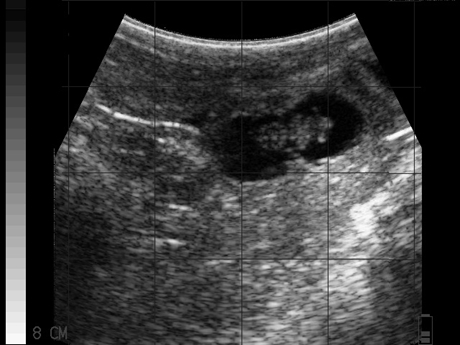

BCF_Easi-Scan_Curve_Bovine_37_Day_Pregnancy